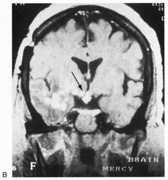

Fig. 10. Striate quadrantanopia. A. A 68-year-old woman with a stroke 3 years previously, causing left inferior quadrantanopia. B. MRI shows infarct of the superior bank of the right calcarine cortex.

The upper and lower banks can also be involved separately. Ischemia can do this because the banks have separate blood supplies. Upper bank infarcts cause homonymous contralateral inferior quadrantanopia (Fig. 10) and lower bank infarcts cause superior quadrantanopia. Although altitudinal defects have been reported occasionally,47,48 most quadrantic defects do not align at the horizontal meridian, because the upper field merges without interruption into the lower field in the depths of the calcarine fissure. Thus it has been argued that quadrantic defects that respect the horizontal meridian are caused by involvement of area V2, surrounding striate cortex,49 which remains controversial. Quadrantanopias are three times more common with striate lesions than with optic radiation lesions.33 Striate quadrantanopias are more frequently isolated signs but can be associated with other signs of higher cortical visual dysfunction, such as pure alexia or hemiachromatopsia, whereas optic radiation quadrantanopias usually are accompanied by hemiparesis, dysphasia, or amnestic problems.33